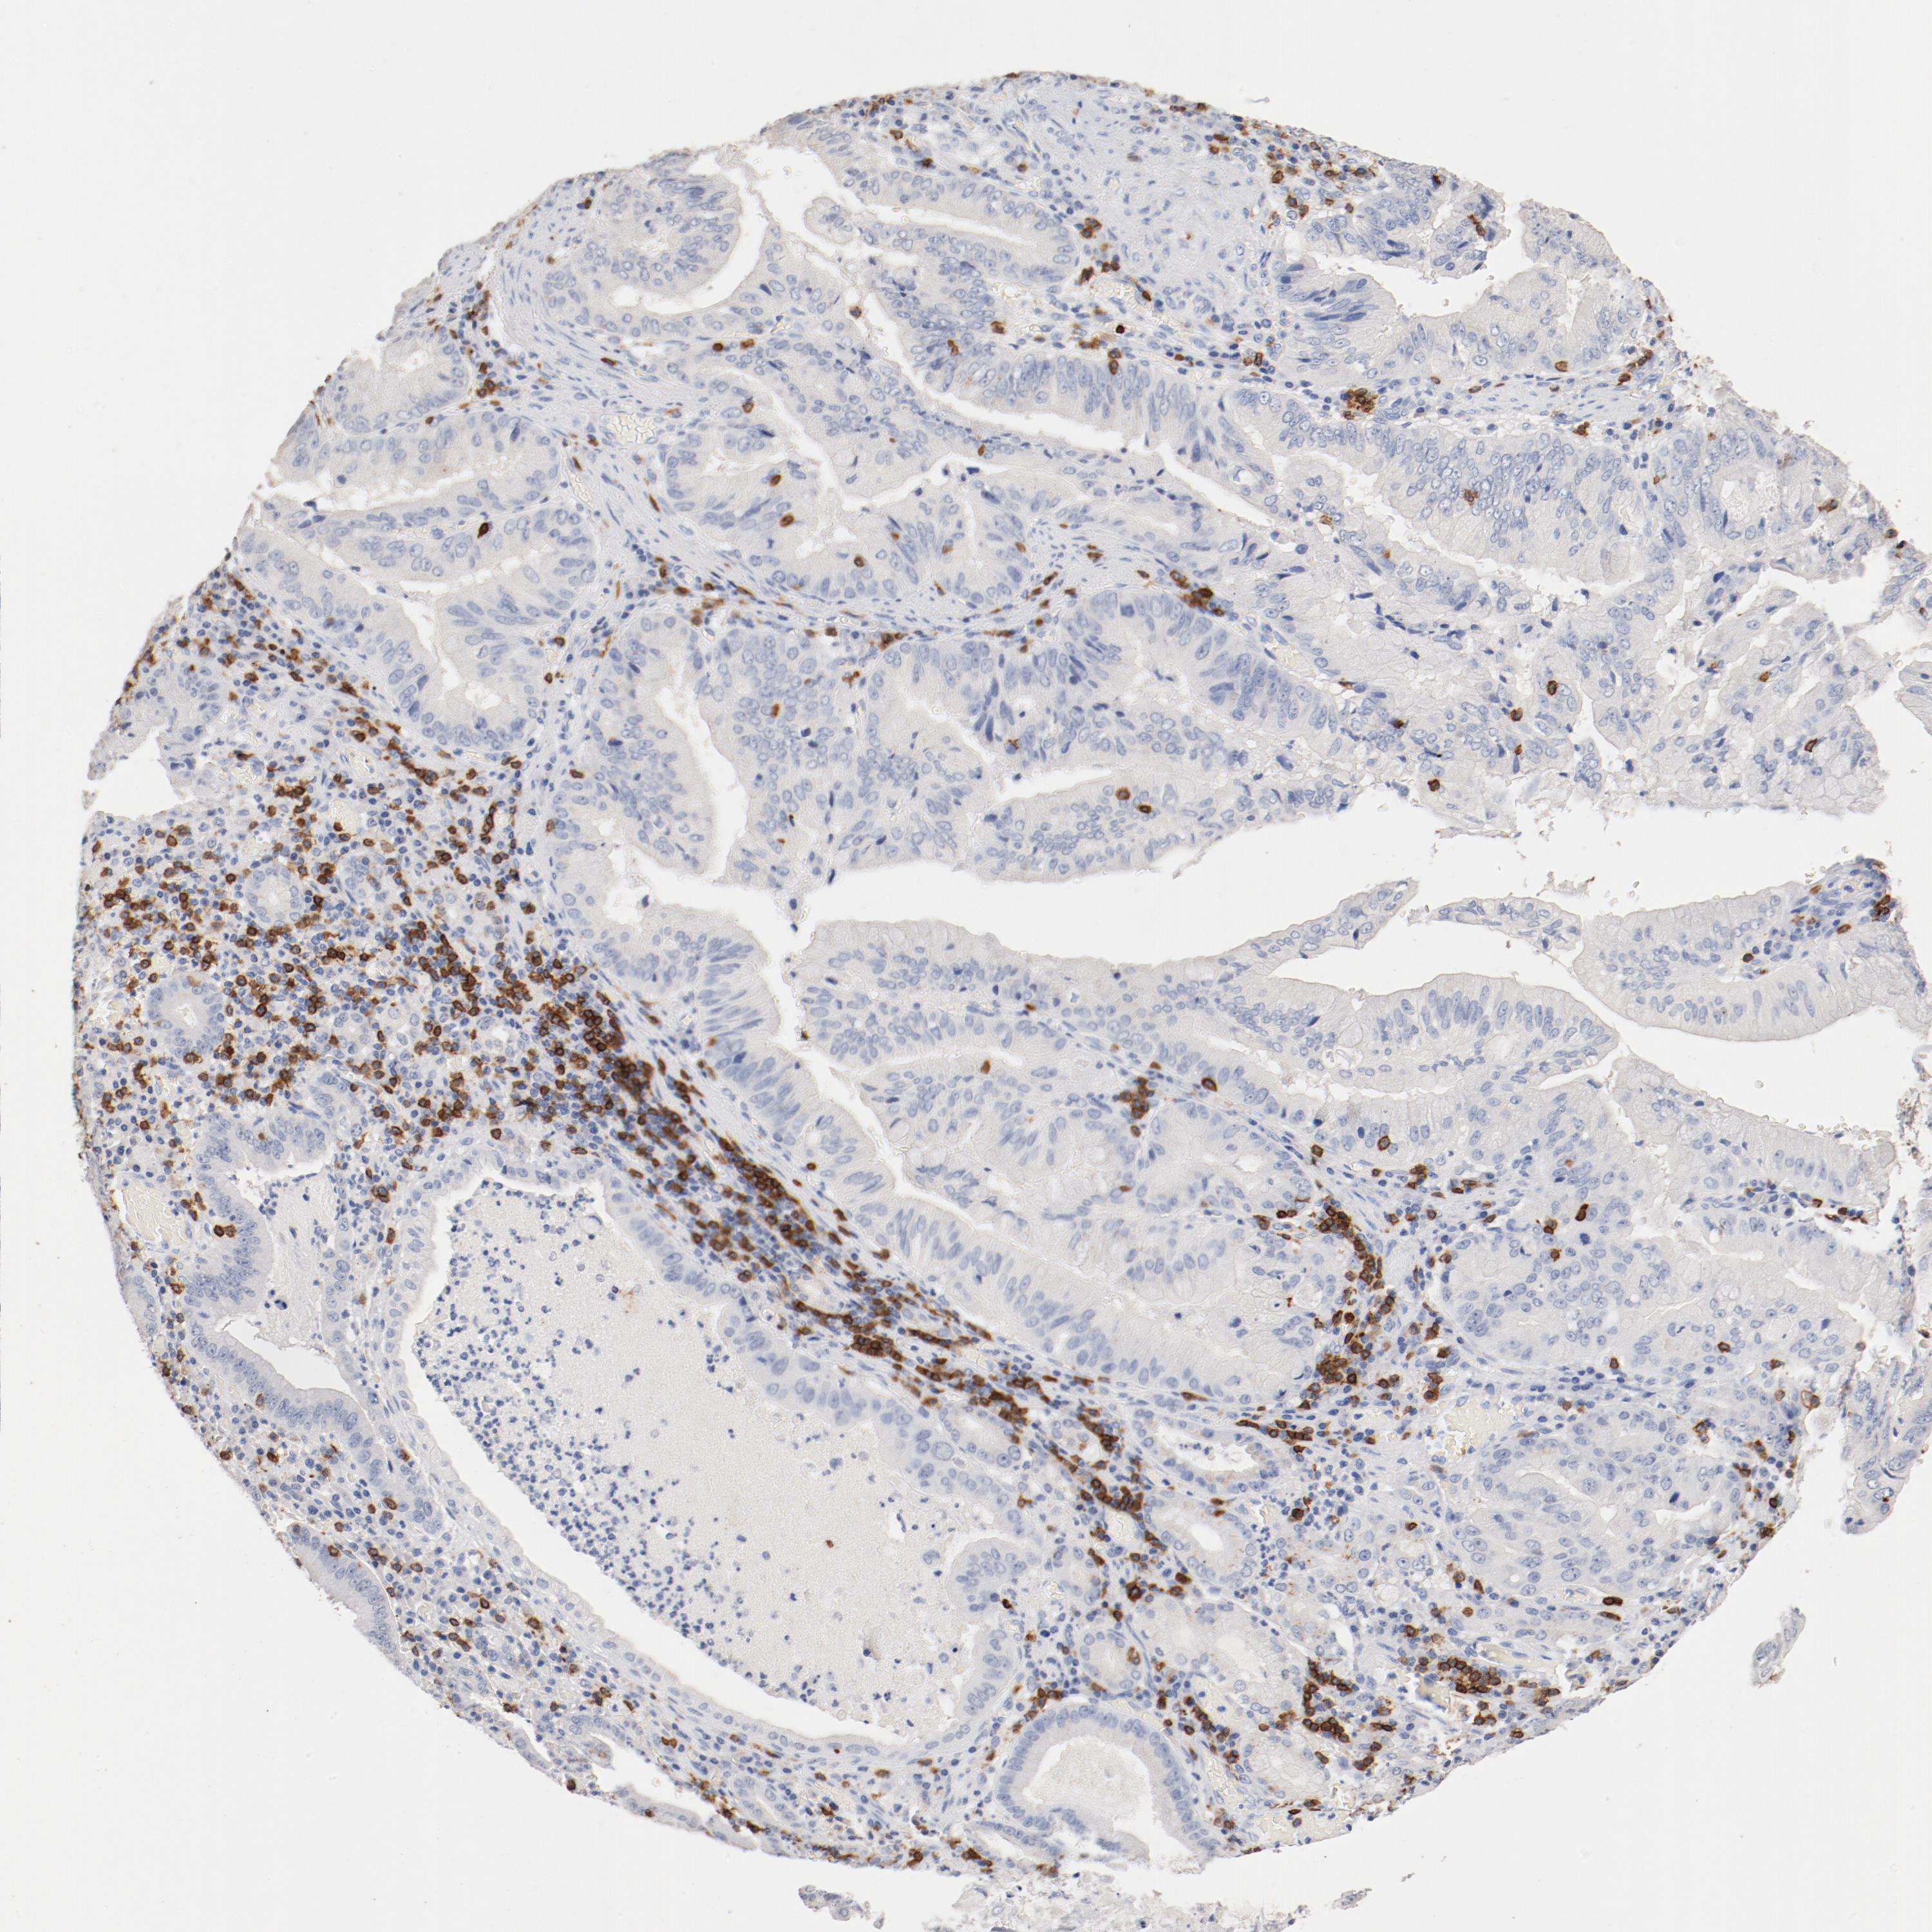

STOMACH CANCER - Protein expressioni

A mouse-over function shows sample information and annotation data. Click on an image to view it in a full screen mode. Samples can be filtered based on level of antibody staining by selecting one or several of the following categories: high, medium, low and not detected. The assay and annotation is described here.

Note that samples used for immunohistochemistry by the Human Protein Atlas do not correspond to samples in the TCGA dataset.

Antibody stainingi

Antibody staining in the annotated cell types in the current human tissue is reported as not detected, low, medium, or high, based on conventional immunohistochemistry profiling in selected tissues. This score is based on the combination of the staining intensity and fraction of stained cells.

Each image is clickable and will lead to virtual microscopy that enables deeper exploration of all samples and also displays staining intensity scores, fraction scores and subcellular localization as well as patient and tissue information for each sample.

Antibody HPA008750

Antibody CAB004651

Staining

High

Medium

Low

Not detected

Intensity

Strong

Moderate

Weak

Negative

Quantity

>75%

75%-25%

<25%

None

Location

Nuclear

Cytoplasmic/membranous

Cytoplasmic/membranous,nuclear

Adenocarcinoma, NOS

Adenocarcinoma, High grade